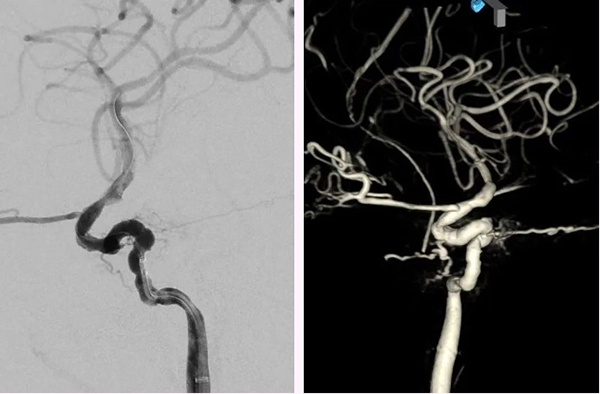

次日,神经外科脑血管病介入团队行DSA检查发现:1.右侧颈内动脉海绵窦段前膝处两个小假性动脉瘤,对应管腔狭窄;2.颈内动脉海绵窦瘘,流量小;3.右侧脑膜中动脉前支供血的脑膜动静脉瘘。鼻出血的“元凶”找到了,就是颈内动脉海绵窦段假性动脉瘤。脑血管病介入团队于全麻下为患者实施了颈动脉覆膜支架置入术,术中采用了“特洛伊木马”技术,利用中间导管将Willis覆膜支架(4.0*10)输送至病变处,精准定位,球囊充盈后,支架贴壁良好,术后即刻造影,假性动脉瘤消失。

▲术后即刻造影见假性动脉瘤消失